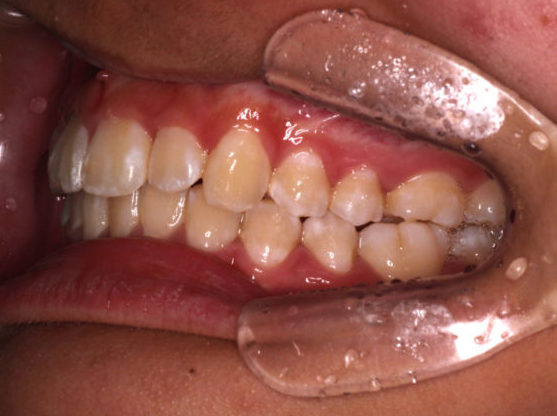

カリエールモーションが終わった時の口腔内写真です。

上の奥歯が後ろに下がったおかげで前歯には隙間ができています。

左の噛み合わせを見ると下の歯と歯の間に上の歯が入り込んでいることがわかります。

1歯対2歯の関係です。

右の噛み合わせを見ると左の噛み合わせより少し多めに奥歯を後ろに下げていることがわかります。

オーバーコレクションといって少し戻ることを想定して多めに動かしておくことを言います。